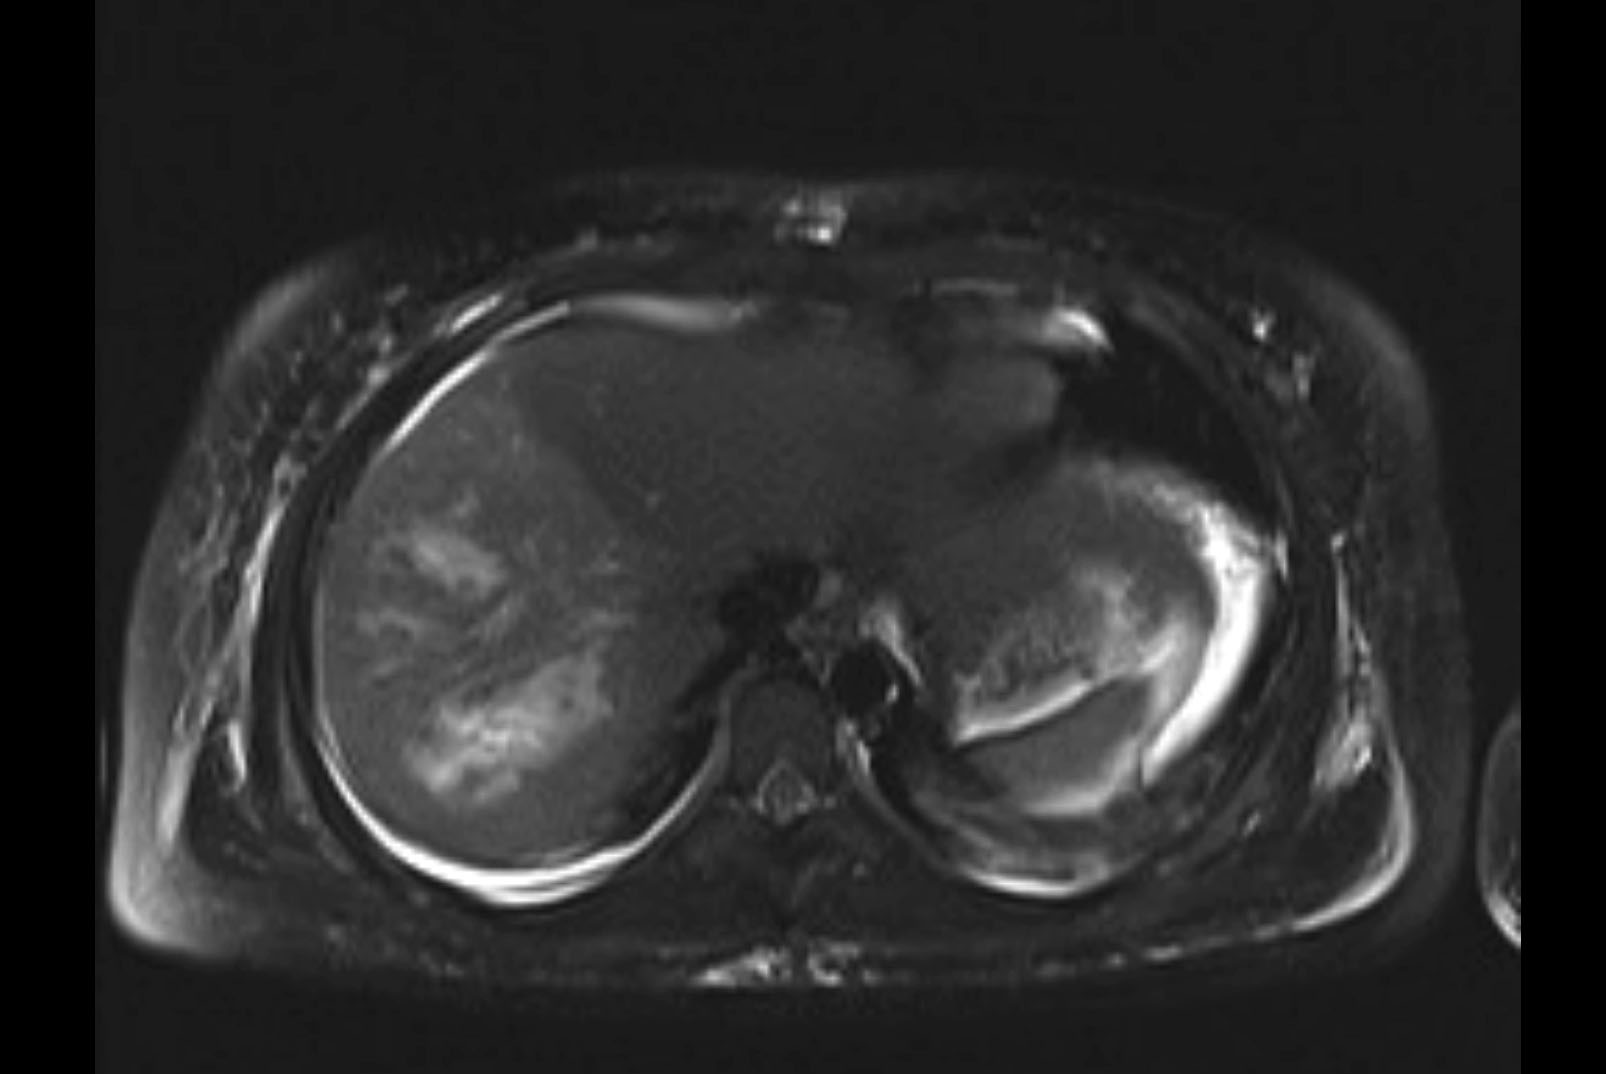

Imaging Analysis

Look through the patient's CT scan to identify any areas of concern for the necessary procedure.

MRI T1

Based on initial findings, which issue(s) would you be most concerned about?